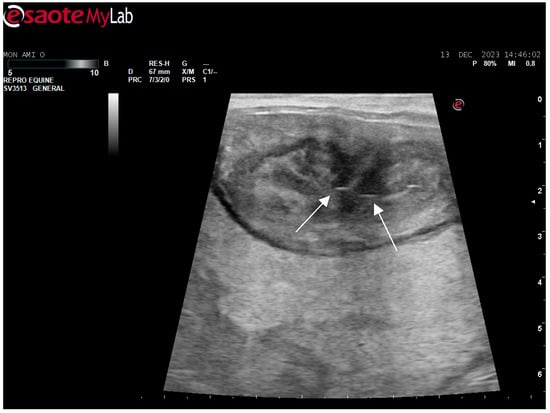

After surgery, the mare’s reproductive system was investigated. Ultrasonographically, slight uterine edema (grade 1 out of 5) and hyperechoic particles (Figure 2), suspected as air in the uterus, were observed. The left ovary was normal in size and echogenicity, present with some 10 to 28.4 mm follicles (Figure 3 and Figure 4). Due to poor perineal conformation, the mare had pneumovagina. Caslic’s vulvoplasty was performed.

Figure 2. Uterine edema (grade 1 out of 5) and hyperechoic particles (white arrows), suspected as air in the uterus.

Animals 14 01307 g002